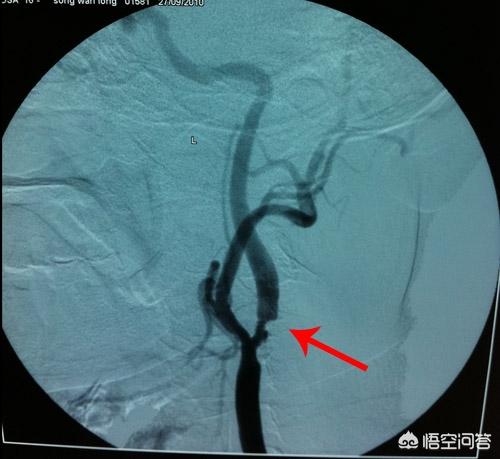

Toutefois, dans la pratique clinique, la thrombose de la carotide commune se produit généralement au niveau de la bifurcation de l'artère carotide commune.(voir ci-dessus)Les caillots sanguins les plus fréquemment bloqués se trouvent dans les artères carotides internes et rarement dans les artères carotides externes, ce qui a beaucoup à voir avec l'approvisionnement en sang de notre cerveau !

Quel est l'apport sanguin au cerveau ?

L'irrigation sanguine du cerveau provient principalement de l'artère carotide interne et de l'artère vertébrale, qui forment une structure appelée anneau artériel cérébral lorsqu'elles pénètrent dans le crâne.(comme indiqué ci-dessus)L'artère carotide interne alimente en sang les hémisphères cérébraux antérieur et moyen, tandis que les artères vertébrale et basilaire alimentent en sang le cervelet et les fosses occipitale et postérieure du cerveau. Le sang injecté dans l'artère carotide interne n'alimente généralement que l'hémisphère cérébral ipsilatéral, et il n'y a pas de croisement vasculaire entre les deux hémisphères cérébraux.Par conséquent, lorsqu'un côté de l'artère carotide interne est bloqué, cela ne provoque souvent que des symptômes d'ischémie cérébrale ipsilatérale。

Ainsi, lorsque la carotide (artère carotide interne) est bloquée, c'est bien le cerveau qui réagit le plus fortement !